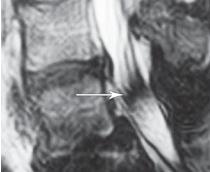

Для лучшего понимания того, что именно может собой представлять стеноз позвоночного канала, обратимся к визуальному сравнению МРТ снимков. Напомню, что нормальный сагиттальный размер позвоночного канала в поясничном отделе позвоночника должен быть не менее 15 мм; от 15 мм до 11 мм — относительный стеноз; менее 10 мм — абсолютный стеноз.

Иллюстрация к книге — Остеохондроз для профессионального пациента [i_076.jpg]

МРТ № 42 — снимок приведён в качестве «нормы» для дальнейшего сравнения снимков поясничного отдела позвоночника.

На МРТ № 43 наблюдается поясничный отдел позвоночника с врождённым (первого типа) абсолютным стенозом позвоночного канала.

На МРТ № 44 наблюдается поясничный отдел позвоночника с приобретённым (второго типа) абсолютным стенозом позвоночного канала.

Если Вы внимательно посмотрите на МРТ № 44, то увидите, как «обычный» дегенеративно-дистрофический процесс может привести к развитию абсолютного стеноза (второго типа) с полным сдавлением спинномозгового канала на уровне LII—LIII и LIV-LV, костными разрастаниями и ретролистезом (смещение позвонка кзади) тела LV поясничного позвонка. Естественно, что у данного пациента серьёзные проблемы с нижними конечностями («параплегия» — паралич обеих ног) и нарушения функции тазовых органов. Единственное, что может ещё помочь больному в этом случае, это хирургическая операция — декомпрессия позвоночного канала. Кстати говоря, первая подобная операция, так называемая декомпрессивная ламинэктомия на поясничном отделе позвоночника, была выполнена в 1900 г. пациенту с подобными нарушениями. И опять-таки мы сталкиваемся с тем, что лучше не допускать развитие заболевания, чтобы потом не оказалось слишком поздно что-либо исправить нехирургическим путём. Есть хорошее выражение: «Тот не мудр, кто из науки себе пользы не извлекает».